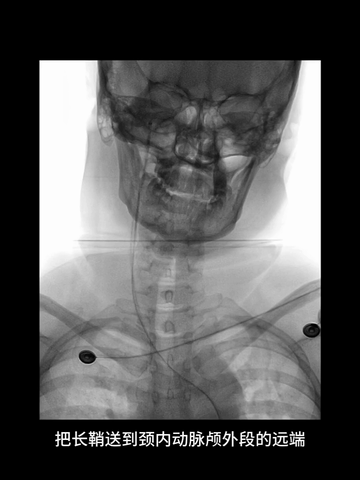

耐心冒烟下,调整导管头在无名动脉内指向左侧,同时回拉导管,进入右CCA,后上高导丝,长鞘沿5F管顺利进入右CCA,后在导管导丝导引下,长鞘头端上高到右C1远端,建立可靠的治疗通路。

6F中间管先送至长鞘头端,而后在微导管(Rebar 18)微导丝(synchro)引导下进入海绵窦段,而后微导丝越过虹吸段进入MCA近端。

正位透视下,微导管配合,微导丝超选进入M2,侧位透视导丝符合下干走形后,微导管跟进到下干远段,造影确认位于真腔。